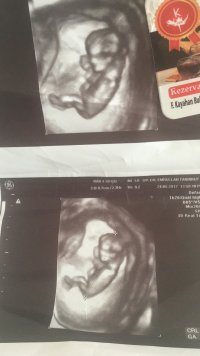

İ İlknuresma84 Yeni Üye Üye 27 Haziran 2017 #298 Banada bakarmısınız Ekli dosyalar 20170626_160350.jpg 675,4 KB · Görüntüleme: 576 20170626_160338.jpg 714,5 KB · Görüntüleme: 578

Uzman SühaN Administrator 27 Haziran 2017 #300 Merhaba görsel net değil nub çıkıntısı görünmüyor bu yüzden durumunuzu değerlendiremiyoruz..